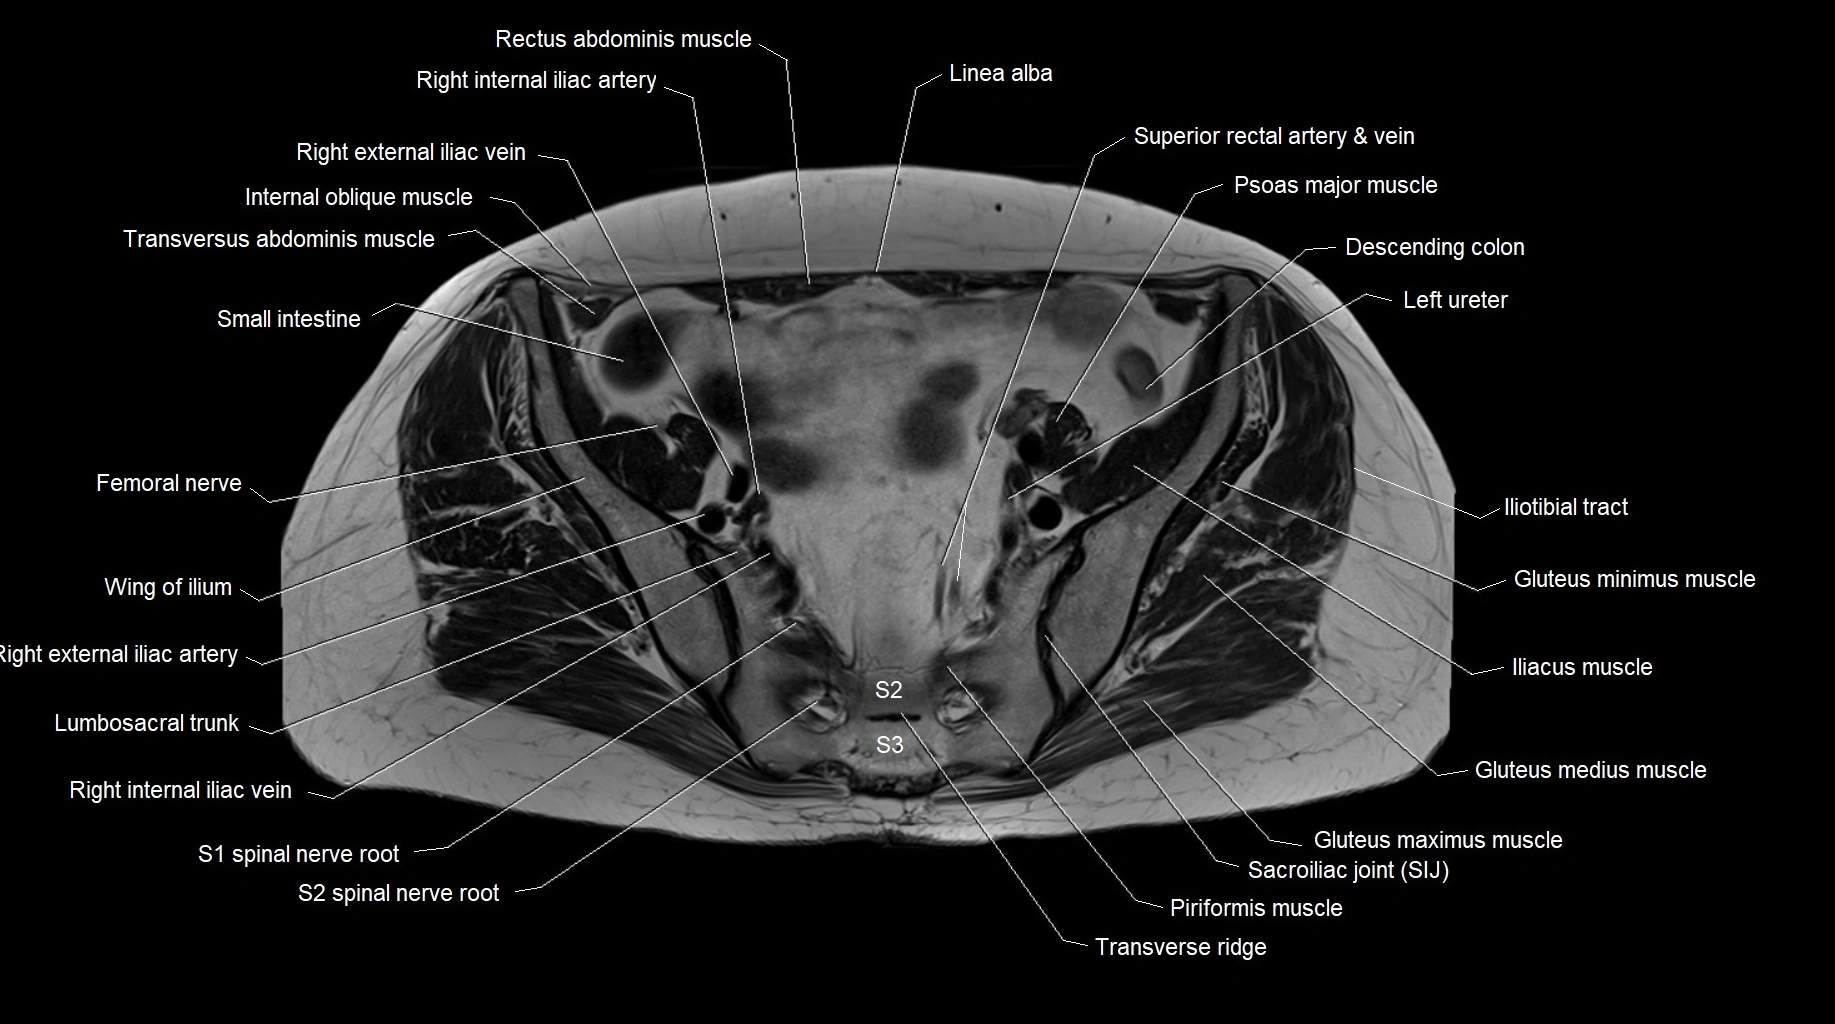

MRI images